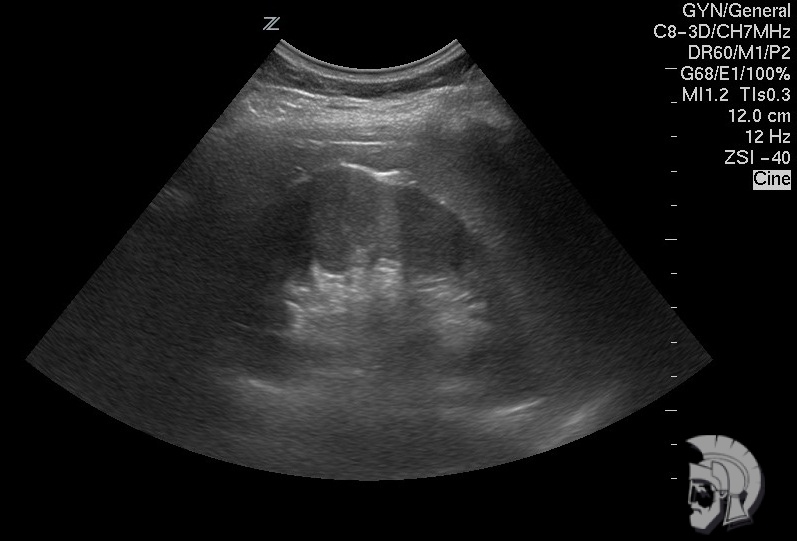

Фото почки.

| Фото здоровой почки мужчины 35 лет |

| Фото правой почки мужчины 39 лет с хроническим пиелонефритом и стажем заболевания 10 лет |

| Фото мочевого пузыря. Кристаллы солей в мочевом пузыре |